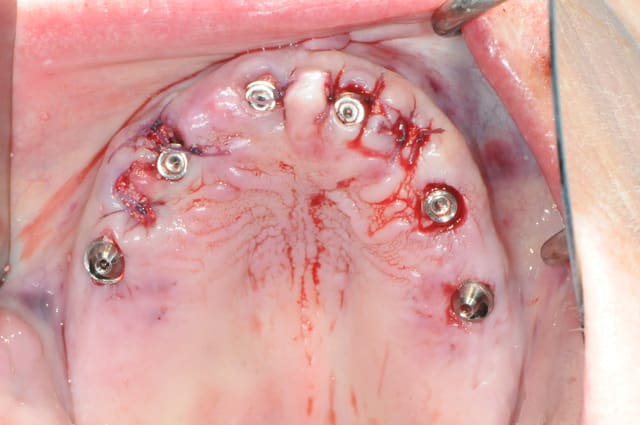

voici un cas en images, j'espère que ça plaira, ça fait un moment que je n'ai rien posté sur nonol et suis en manques de critiques et de compliments.

la patiente a été opérée hier et j'ai mis ses prothèses aujourd'hui.

je remercie Rachel et Arnaud qui se sont prêtés à la délicate tâche de l'assistante opératoire.